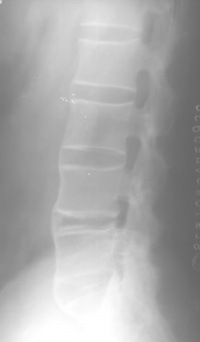

强直性脊柱炎患者X光照片

强直性脊柱炎(ankylosing spondylitis)是一种慢性全身性炎性疾病,它的病因不明,主要侵犯脊柱,尤以骶髂关节病变最为常见。它的最为显著的变化为关节纤维化和骨性强直,引起骨性强直及畸形。累及髋关节者占1/4,偶可累及膝、踝及手足小关节。有遗传因素。寒冷及潮湿地区多见。男性青壮年多见。人类白细胞抗原HL-B1280% 阳性。X射线可见椎体骨质疏松,边缘相连成骨桥,但是仍呈方形及保留椎间隙。治疗重点是缓解 疼痛,防治畸形。截骨术可矫正脊椎驼背畸形、关节屈曲挛缩或融合畸形。还可做人工关节置换术。

在脊柱方面主要表现在椎间盘、脊椎小关节、肋脊关节,后纵韧带寰枢关节。很少有上述关节出现病变而骶髂关节却不受侵犯。早期阶段,椎间盘纤维环浅层有炎症,伴反应性骨硬化与邻近椎体腐蚀,使椎体变成方形。纤维环逐渐骨化,并有骨桥形成。同时脊椎后关节和邻近韧带亦有类似的变化,最终脊柱完全融合,如竹节状(图96-10)。